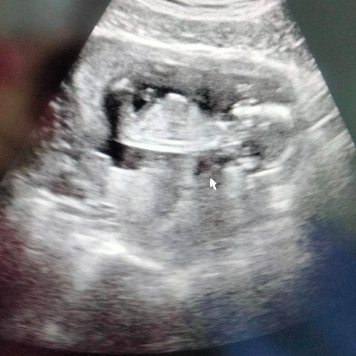

โสรยา พรมหล้า มือเซตทีมชาติไทย ประกาศแสดงความดีใจหลังตั้งครรภ์ได้ 3 เดือน

โสรยา พรมหล้า มือเซตทีมชาติไทย ประกาศแสดงความดีใจหลังตั้งครรภ์ได้ 3 เดือน โดย โสรยา พรมหล้า ได้โพสต์ลง Facebook : Promla Soraya ระบุใจความว่า “เบบี๋ 3 เดือนกว่าแล้วววว”

โส พึ่งรู้ว่าโสมีเจ้าตัวน้อยไม่กี่วันที่ผ่านมา โสไม่เคยรู้เลยว่าเจ้าตัวน้อยไปแข่งซีเกมส์กับโสช่วยพาทีมคว้าแชมป์ด้วย แถมยังร่วมฝึกซ้อมทีมชาติกับโสมาหลายเดือน และยังได้มีโอกาสเล่นกับทีมระดับโลกอย่างบราซิลด้วย มัมมี่ว่าถ้าหนูเกิดมา ไม่มีใครเล่นวอลเลย์เก่งเท่าหนูแน่เลย(ว่าแต่ทีมเราเล่น 7 คนในสนามจะผิดมั้ยเนี่ย)